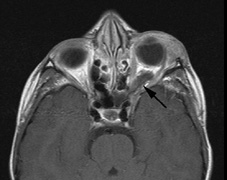

Optic nerve gliomas may involve the optic chiasm and be associated with endocrine disorders or nystagmus.68–70 Surgical excision of chiasmal gliomas (Fig. 6) carries a high risk of visual loss. Invasion of the hypothalamus or the third ventricle carries a poor prognosis, with greater than 50% 15-year mortality rate.71 One review of radiation treatment for chiasmal gliomas collated data from small case series and found no significant long-term improvement in visual function, progression, or mortality with radiation treatment.71 Other reports suggest that radiation doses over 4500cGy improve symptoms and slow progression of chiasmal gliomas over several years.72 Adequate tumor coverage by radiotherapy results in irradiation of normal brain and nearly all children need hormone replacement.73 Chemotherapy is an alternative.74,75

Fig. 6. Surveillance images of a 12-year-old girl with NF1 and an optic nerve glioma which has extended to involve the chiasm. Pre- (a) and postcontrast (b) T1-weighted coronal images reveal a large suprasellar mass with an enhancing component (arrow) seen separately from the normally enhancing pituitary gland. (c) Axial scans through the suprasellar cistern show the tumor is high signal on T2-weighted scans. (d) Enlargement of the chiasm, optic nerve and hypothalamus is visible on the post-contrast T1-weighted sagittal image. Although optic nerve glioma usually has a good prognosis (with visual function often remaining stable in the absence of any intervention66,67), chiasmal involvment is a poor prognostic indicator. A sign of chiasmal involvment may be new onset of endocrine disorders or nystagmus. Surgical excision of chiasmal gliomas carries a high risk of visual loss.68–70